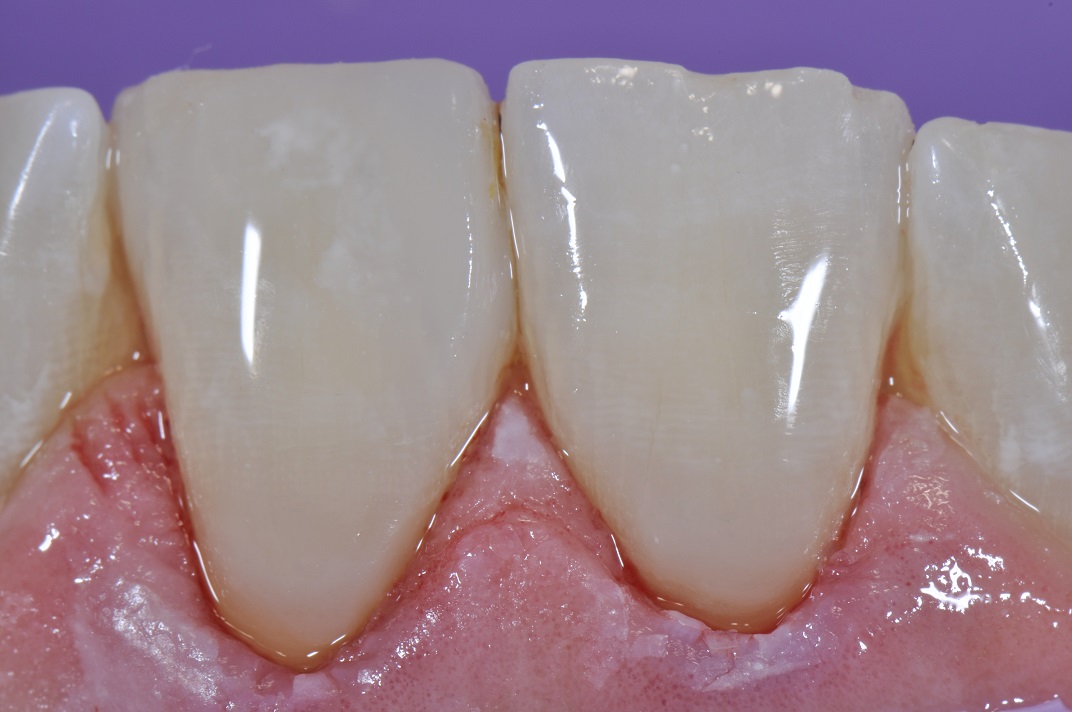

Class V seamless bonded restorations What Is A Class V Restoration In Dental — class iii, iv, and v direct composite restorations are mainly indicated in the restoration of caries lesions (class iii, iv, and v), anterior enamel. Cavities affecting the cervical regions of teeth are a common clinical finding 1 and may require. class v composite restoration failures lie in overconfidence with dentin bonding, a complete lack of standardized preparation. What Is A Class V Restoration In Dental.